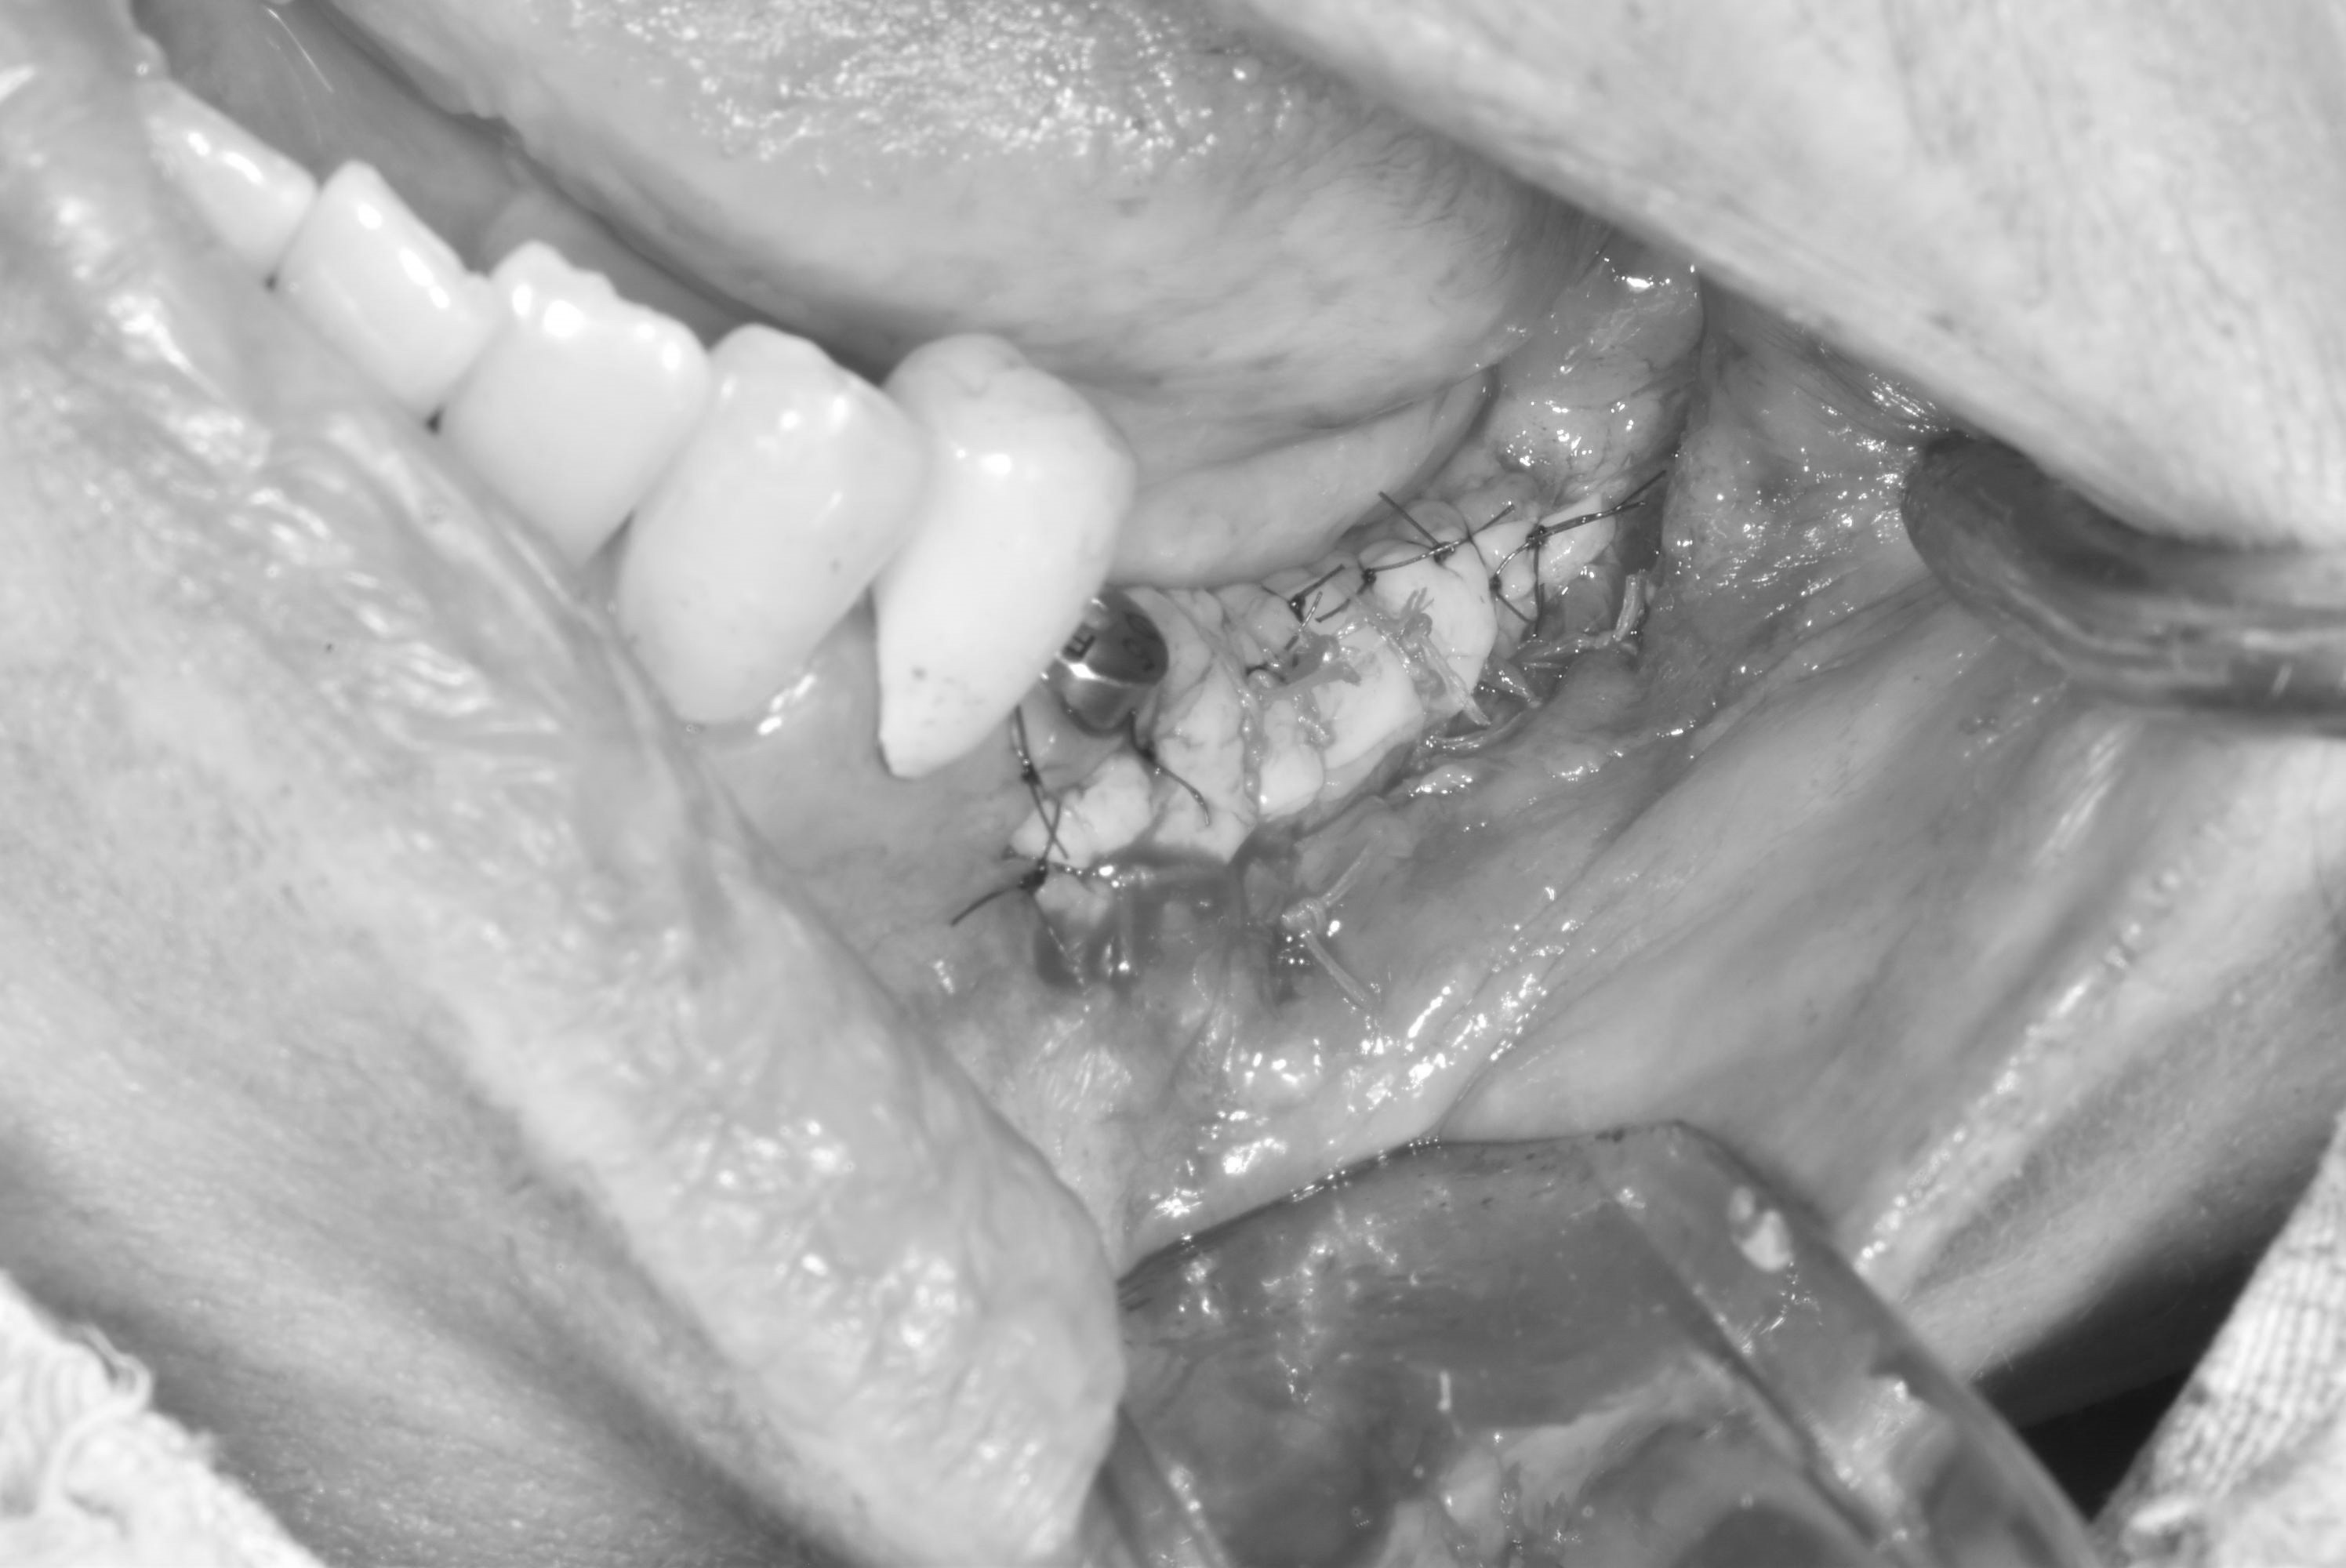

牙齦移植術(補肉)

案例三